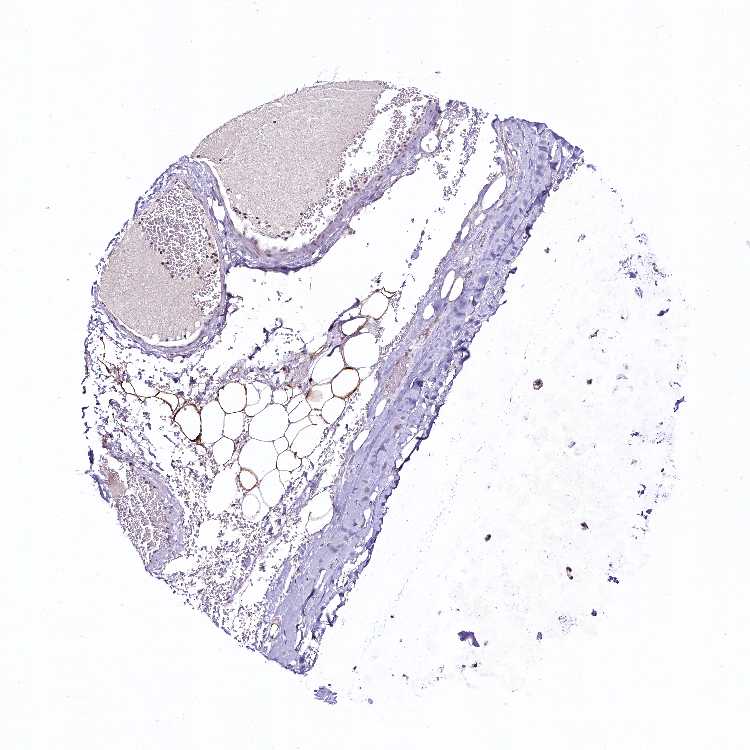

SOFT TISSUE 1 - Antibody stainingi

Antibody staining in the annotated cell types in the current human tissue is reported as not detected, low, medium, or high, based on conventional immunohistochemistry profiling in selected tissues. This score is based on the combination of the staining intensity and fraction of stained cells.

Each image is clickable and will lead to virtual microscopy that enables deeper exploration of all samples and also displays staining intensity scores, fraction scores and subcellular localization as well as patient and tissue information for each sample.

Antibody HPA041409Antibody HPA041482

Chondrocytes -Low

Fibroblasts MediumNot detected

Peripheral nerve MediumNot detected